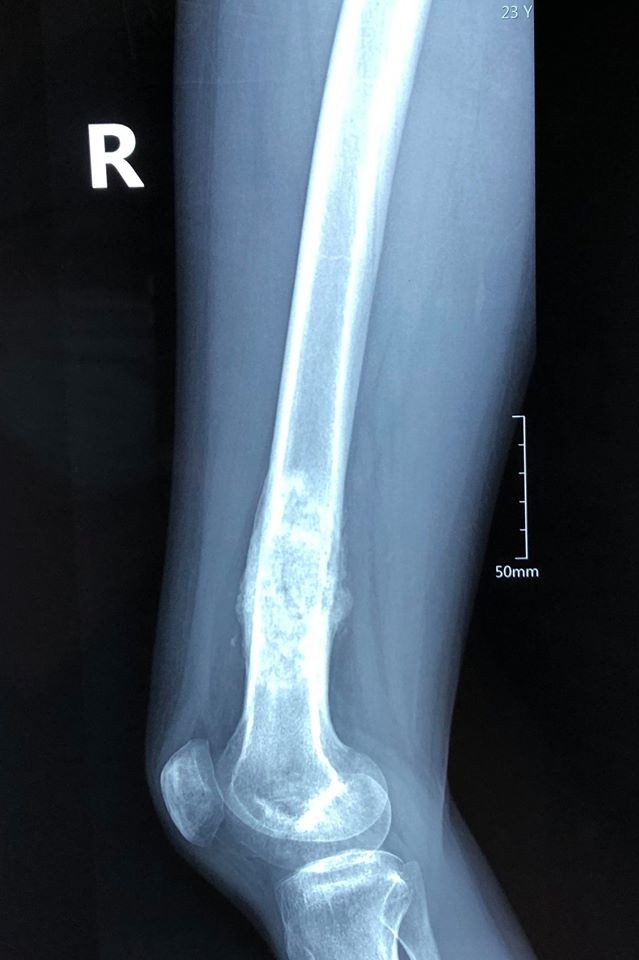

Một năm trở lại đây, chân phải của H. thỉnh thoảng bị đau dọc theo thân xương đùi, đau tăng lên vào buổi tối và khi vận động nặng. Nhìn bề ngoài chân phải của H. không bị sưng đau hay biến dạng, vận động gối hoàn toàn bình thường.

H. đã đi khám ở một số nơi, nhưng bác sĩ không phát hiện ra bệnh. Do đang là sinh viên năm cuối bận rộn, nên cô không đi khám ở chuyên khoa sâu về cơ xương khớp. Một lần về quê, khi chụp Xquang ở bệnh viện tỉnh, các bác sĩ đã phát hiện H. có dấu hiệu bất thường ở xương đùi và chuyển H. lên tuyến trên để chẩn đoán, điều trị.

Ảnh X-quang đùi phải của bệnh nhân H. khi phát hiện ung thư xương ác tính. Ảnh: Sơn Tùng

Tháng 6/2019, sau khi được chẩn đoán giải phẫu tại Bệnh viện K Tân Triều, cô sinh viên nhận được tin dữ - bị ung thư xương ở mức độ ác tính cao. Lúc này, khối u đã lan ra toàn bộ xương đùi của H. mặc dù cô phát hiện tương đối sớm.

Theo các bác sĩ, các ca ung thư khác chỉ ung thư ở một phần của xương, nhưng trường hợp này cả phần dưới và phần trên xương đùi đều có dấu hiệu của ung thư. Vì thế, phác đồ điều trị phải hoàn toàn khác so với các ca thay khớp trước đó. Bởi việc thay xương đùi có liên quan trực tiếp đến hai khớp lớn của cơ thể vô cùng phức tạp.